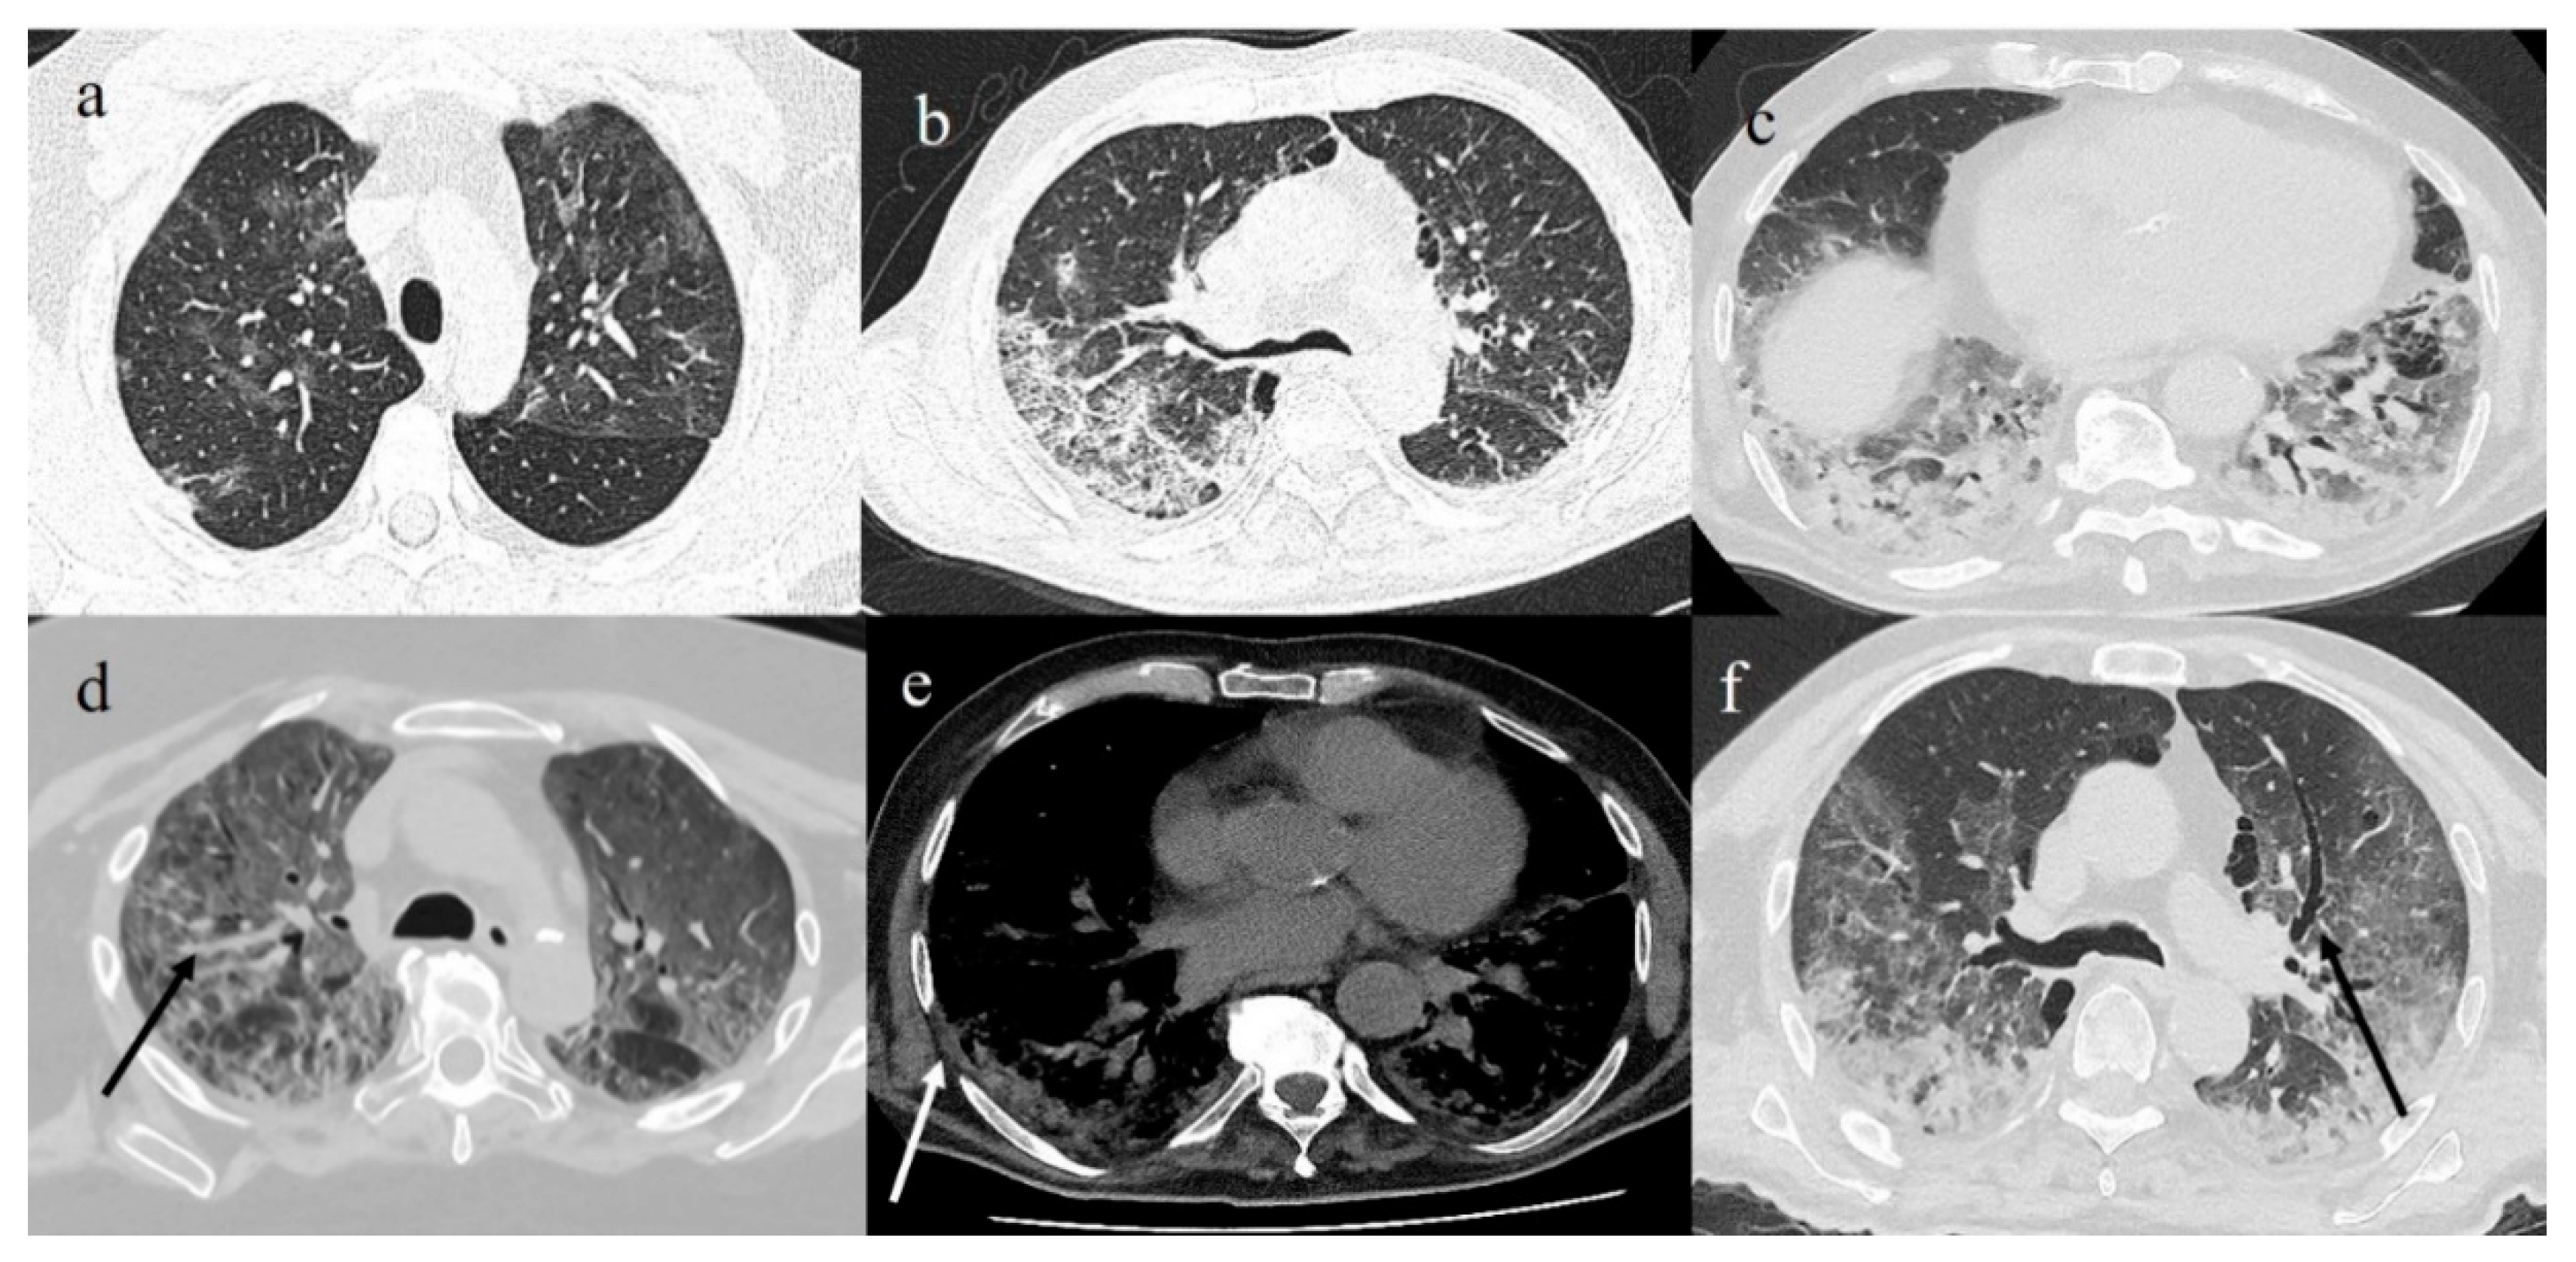

4. Chest CT

4.3. COVID-19 CT Features and Reporting System

4.4. COVID-19 Pneumonia CT Staging

4.5. CT Severity Scores as Prognostic and Predictive Indicators of Clinical Outcome

- Li, K.; Fang, Y.; Li, W.; Pan, C.; Qin, P.; Zhong, Y.; Liu, X.; Huang, M.; Liao, Y.; Li, S. CT image visual quantitative evaluation and clinical classification of coronavirus disease (COVID-19). Eur. Radiol. 2020, 30, 4407–4416. [Google Scholar] [CrossRef] [PubMed]

- Fu, F.; Lou, J.; Xi, D.; Bai, Y.; Ma, G.; Zhao, B.; Liu, D.; Bao, G.; Lei, Z.; Wang, M. Chest computed tomography findings of coronavirus disease 2019 (COVID-19) pneumonia. Eur. Radiol. 2020, 30, 5489–5498. [Google Scholar] [CrossRef]

- Ojha, V.; Mani, A.; Pandey, N.N.; Sharma, S.; Kumar, S. CT in coronavirus disease 2019 (COVID-19): A systematic review of chest CT findings in 4410 adult patients. Eur. Radiol. 2020, 30, 6129–6138. [Google Scholar] [CrossRef]

- Zhou, S.; Zhu, T.; Wang, Y.; Xia, L. Imaging features and evolution on CT in 100 COVID-19 pneumonia patients in Wuhan, China. Eur. Radiol. 2020, 30, 1–9. [Google Scholar] [CrossRef] [PubMed]

- Simpson, S.; Kay, F.U.; Abbara, S.; Bhalla, S.; Chung, J.H.; Chung, M.; Henry, T.S.; Kanne, J.P.; Kligerman, S.; Ko, J.P.; et al. Radiological Society of North America Expert Consensus Statement on Reporting Chest CT Findings Related to COVID-19. Endorsed by the Society of Thoracic Radiology, the American College of Radiology, and RSNA - Secondary Publication. J. Thorac. Imaging 2020, 35, 219–227. [Google Scholar] [CrossRef] [PubMed]

- Chung, M.; Bernheim, A.; Mei, X.; Zhang, N.; Huang, M.; Zeng, X.; Cui, J.; Xu, W.; Yang, Y.; Fayad, Z.A.; et al. CT Imaging Features of 2019 Novel Coronavirus (2019-nCoV). Radiology 2020, 295, 202–207. [Google Scholar] [CrossRef] [PubMed]